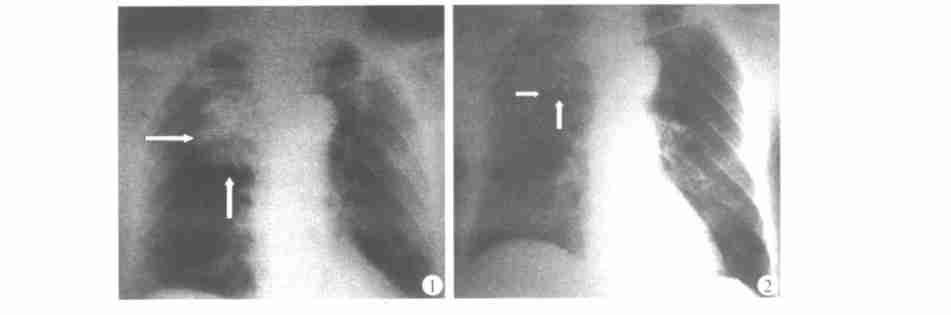

图一 治疗术中的X线片

图二 治疗两周时的X线片